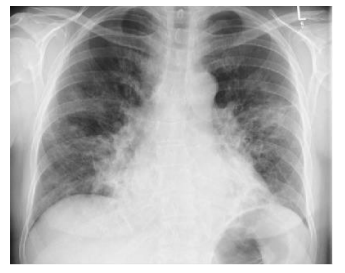

Um paciente de 65 anos, tabagista e etilista, apresentava dor epigástrica com irradiação para o dorso há três semanas, com período de exacerbação pós-prandial, principalmente noturno, e frequente despertar na madrugada com dor e com melhora no período da manhã. Passou a apresentar dor intensa e agitação na última hora, seguida de episódio de hematêmese, evoluindo com quadro de abdômen em tábua.

A radiografia captou a imagem abaixo.

O diagnóstico mais provável para o caso descrito é: